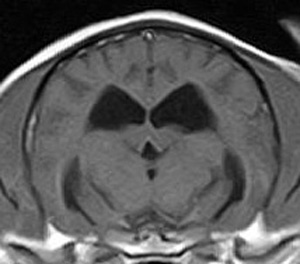

けいれん発作が出るワンちゃんが来院されました。MRI検査では脳に構造上の異常を認めず、特発性てんかんとの診断でお薬での治療となりました。発作は現在のところ、お薬で良好にコントロールされています。